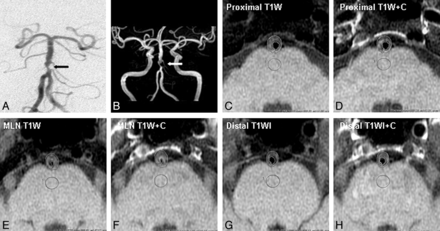

Images from a 66-year-old man with recurrent TIA symptoms of diplopia and left limb weakness for 22 days. A and B, A severe stenosis at the proximal segment of basilar artery is shown on conventional angiography (black arrow) and on MRA (white arrow). DWI demonstrates no recent infarction in the territory of the stenotic basilar artery (not shown). C–H, After matching T1WI and postcontrast T1WI at the section proximal to, at, and distal to the MLN site, the wall enhancement index at the section proximal to, at, and distal to the MLN site was 14%, 29%, and 22%, respectively. The strongest wall enhancement was observed at the section of the MLN site.

Wall enhancement index was used to characterize the extent of wall enhancement. After manually tracing the BA wall, SI of BA plaque (SIplaque) at an unclosed-ring area on matched T1WI and postcontrast T1WI was measured. SI of adjacent normal gray matter (SIgray matter), which was lesion-free in a round area of 18 mm2 on matched T1WI and postcontrast T1WI, was also measured as a reference (Figs 1 and 2). Then the wall enhancement index was calculated as follows: ([SIplaque/SIgray matter on postcontrast T1WI] − [SIplaque/SIgray matter on matched precontrast T1WI])/(SIplaque/SIgray matter on matched precontrast T1WI) × 100%. SIplaque and SIgray matter on matched precontrast and postcontrast T1WI in the initial 10 patients were measured by another pair of reviewers (N.M., L.M.) for estimation of interobserver variability.

Wall enhancement indices for the BA proximal to, at, and distal to the MLN site were 54 ± 53%, 58 ± 42%, and 41 ± 38%, respectively. Wall enhancement index of the section distal to the MLN site was lower than both the proximal section (P = .048) and the section at the MLN site (P = .001). There was no significant difference in the wall enhancement index between the proximal section and the section with MLN (P = 0.566).